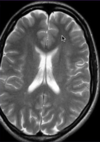

DX?

Infarto cerebral debido a ACM izq